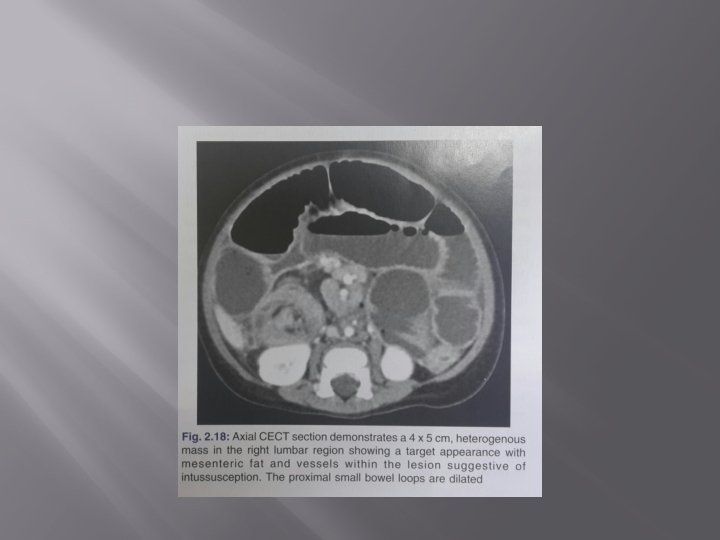

INTUSSUSCEPTION � � � It is most frequently seen in children under 2 years of age. In children it usually commences in the ileum as the result of inflammation of the lymphoid tissue and tends to be associated with mesenteric adenitis. It is usually recognised clinically by pain, vomiting, blood in the stool and a palpable tumour. In adults, an intussusception is invariably caused by a tumour of the bowel, which may be large or small, benign or malignant. Any part of the small bowel may be involved, although the terminal ileum is still the most common site.

� � Plain films try show evidence of small-bowel obstruction, or the intussusception itself may be identified as a soft-tissue mass sometimes surrounded by a crescent of gas and most frequently identified in the right hypochondrium. `Target sign’ comprising two concentric circles of fat density lying to the right of the spine-often superimposed on the kidney. It is due to the layers of peritoneal fat surrounding and within the intussusceptum alternating with the layers of mucosa and muscle but seen `end on’. Barium examination will reveal claw sign.